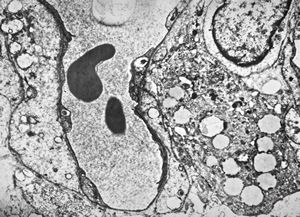

F,68y. | xanthomatous cell in atherosclerotic plaque - a. vertebralis